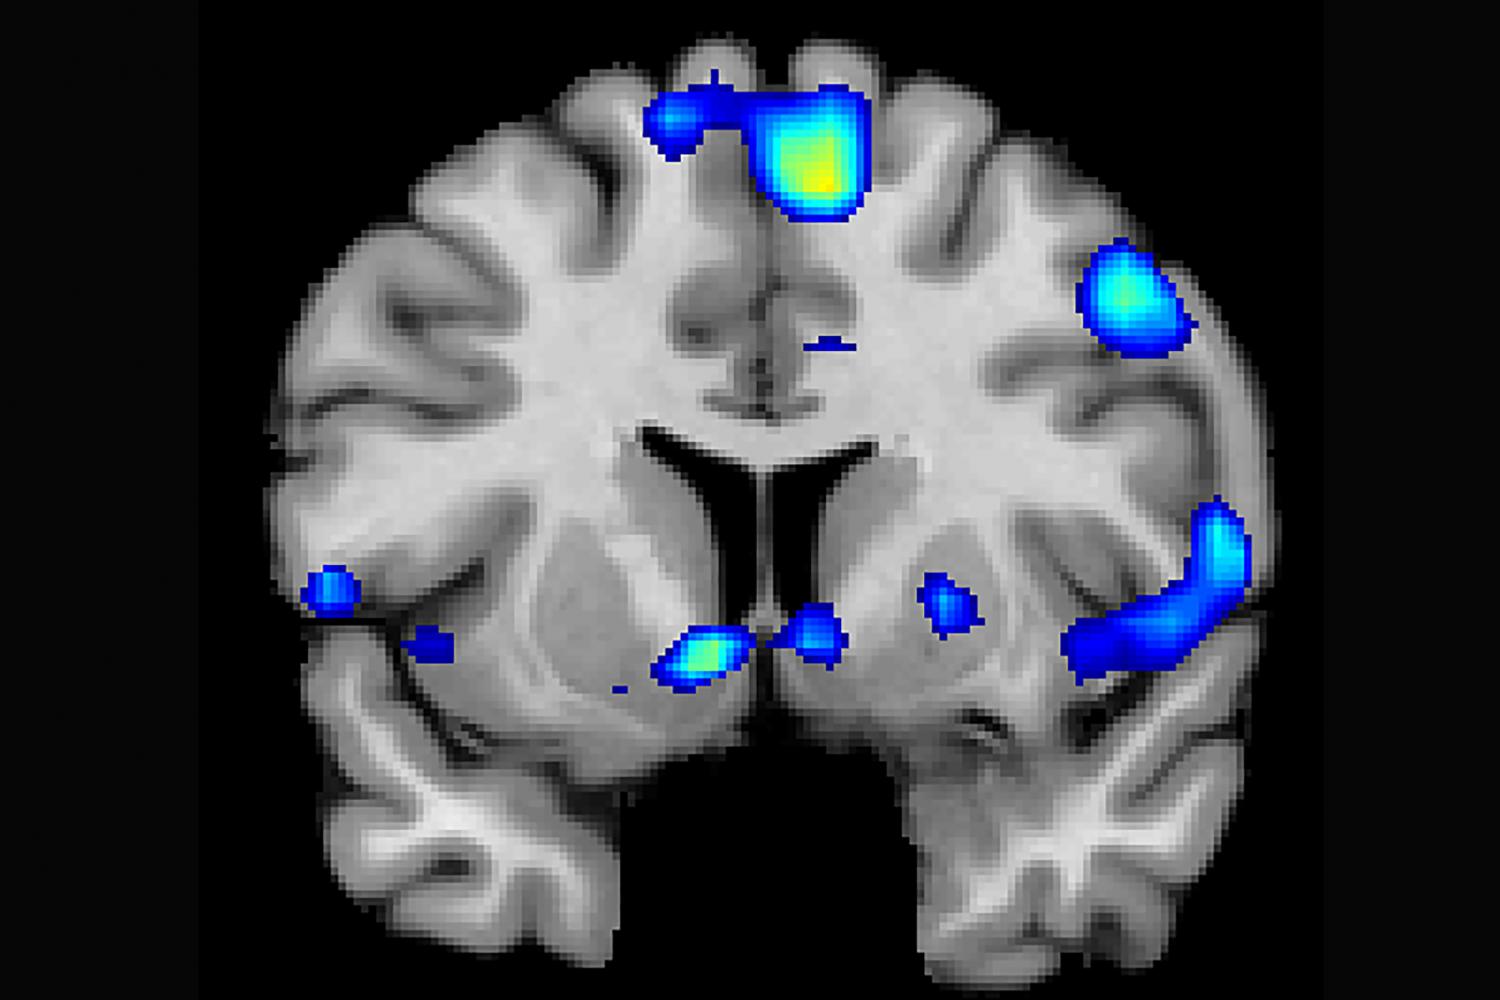

Researchers scan the brains of people having strong spiritual experiences.